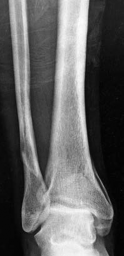

Tibial shaft fracture extending into the plafond—intramedullary fixation Case description a A 25-year-old wom…